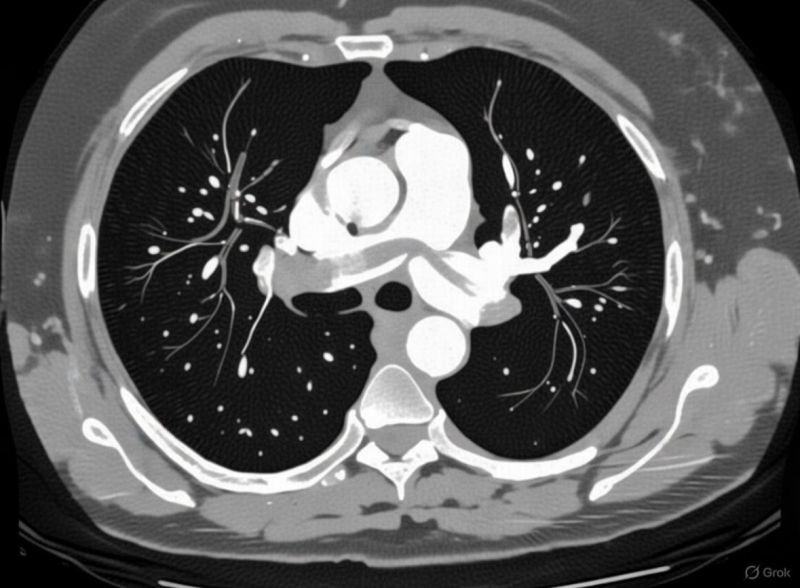

”We still tend to talk about venous thromboembolism like it’s a plumbing problem.

A blockage forms, flow is reduced, pressure builds, and treatment is about reopening the pipe.

But a thrombus isn’t an inert plug. Once it forms, it becomes biologically active.

Clot isn’t just trapped blood.

It retains active thrombin and factor Xa, becomes increasingly resistant to breakdown, and carries a significant inflammatory signal.

Even after anticoagulation is started, the clot itself can continue to drive disease.

In many ways, it behaves more like an organ than debris .

That matters when we think about embolization. When part of a thrombus travels, it doesn’t arrive downstream as a neutral obstruction.

It arrives loaded with active coagulation enzymes and inflammatory mediators. What follows isn’t just blockage, but propagation.

This helps explain why we see pulmonary embolism without an obvious DVT, why clot burden can progress early, and why timing matters so much in VTE care.

Anticoagulation is essential. It prevents new clot from forming. But it doesn’t neutralize the biologic activity of the thrombus that’s already there.

That clot can remain enzymatically active, inflammatory, and emboligenic for far longer than we tend to acknowledge.

This is where total thrombus clearance becomes important, beyond restoring flow.

Removing clot removes the thrombin reservoir, the inflammatory stimulus, and the substrate for ongoing embolization and re-thrombosis.

It’s less about cosmetics on imaging and more about biologic source control.

As we rethink how we treat VTE, the question shouldn’t only be whether flow looks better at the end of the case.

It should be whether the clot has lost its ability to cause harm.”